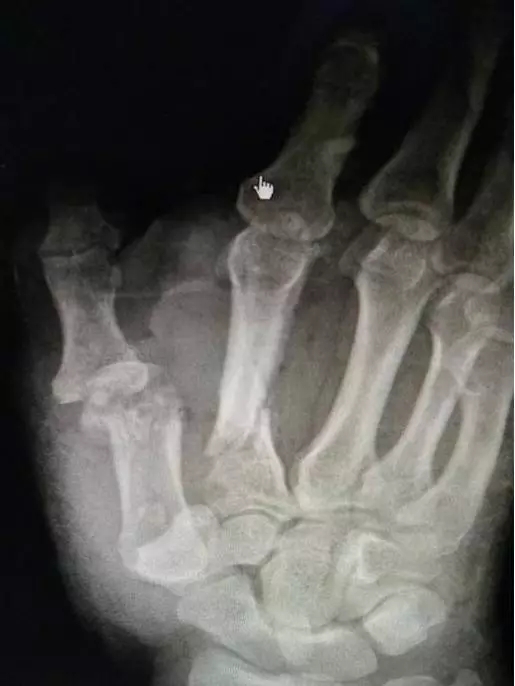

手足外科马忠超主任接诊后,立即为小吴进行了相关检查,诊断结果为右手大量软组织缺损、碎裂严重,污染较重,右手第1、2掌骨骨折外露,并骨质缺损,伴第1腕掌关节及拇掌关节脱位,断端碎裂严重,末端血运感觉较差,情况十分危急。